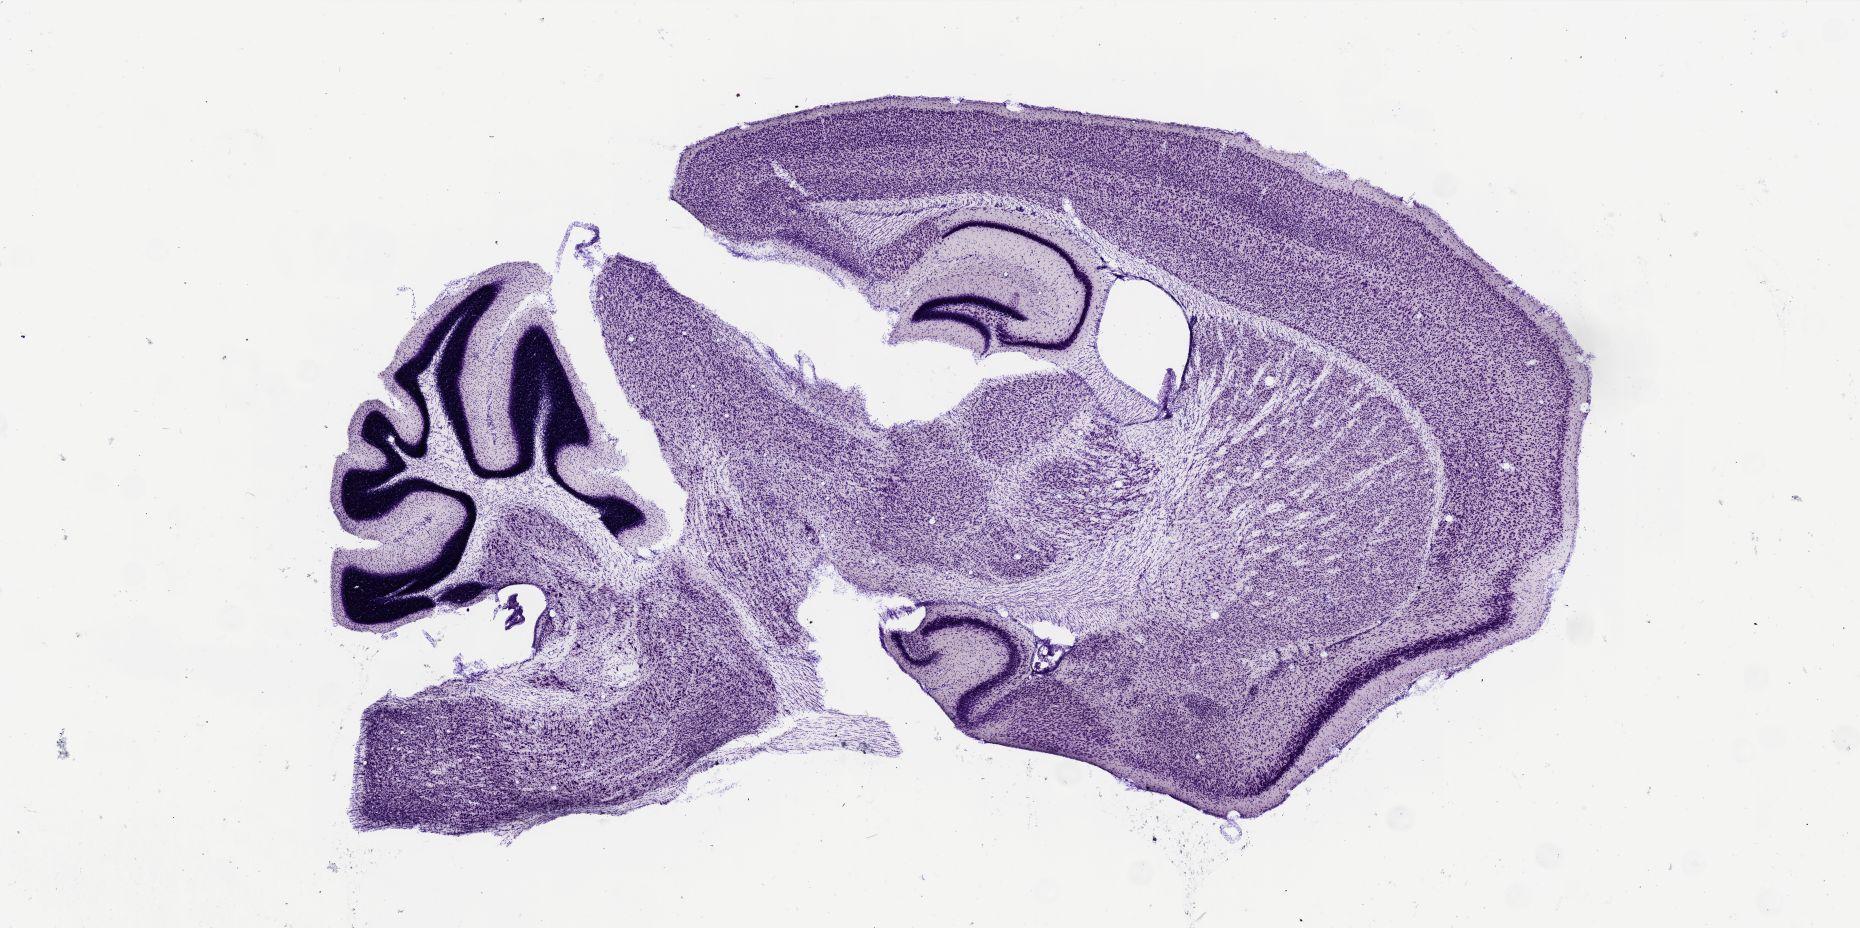

Datasets -> Mus Musculus -> Nissl, sagittal, histo, Whole-Brain, adult

[ Metadata ]   ·   Source: Shawn Mikula

thumbnail

m07c